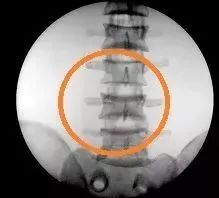

3. 透视的部位对准增强器中心:如果不对准中心,有可能导致成像偏黑甚至出现废片,特别是拍脊柱图像时,正位时比较容易对准,但是侧位时要注意,预想一下椎体位置,保证人体覆盖了至少在 50%~70% 左右的中心位置。

某机器的脊柱正位,侧位正常片,侧位偏离中心后偏暗图像以及和侧位严重偏离中心后导致的废片。注意使用的是体模,和真实人体 X 光片有一定的差别。